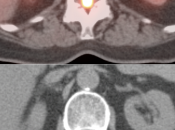

Radiation Necrosis (or Chemonecrosis):

- Necrosis presents months to years after radiation therapy (rarely < 3 months post radiation).

- Difficult to differentiate necrosis from malignancy on MRI, as both demonstrate enhancement.

- Necrosis is typically non-avid on PET images.

- Recurrent malignancy will demonstrate FDG uptake, often focal and involving only a small portion of a surgical cavity. The uptake may be intense (an easy diagnosis) or may be minimally above adjacent background uptake (a more difficult diagnosis, which may require follow-up).

- FDG-avid recurrence should correspond to the area of enhancement noted on MRI (MRI should be done first, with images available at time of PET/CT interpretation).